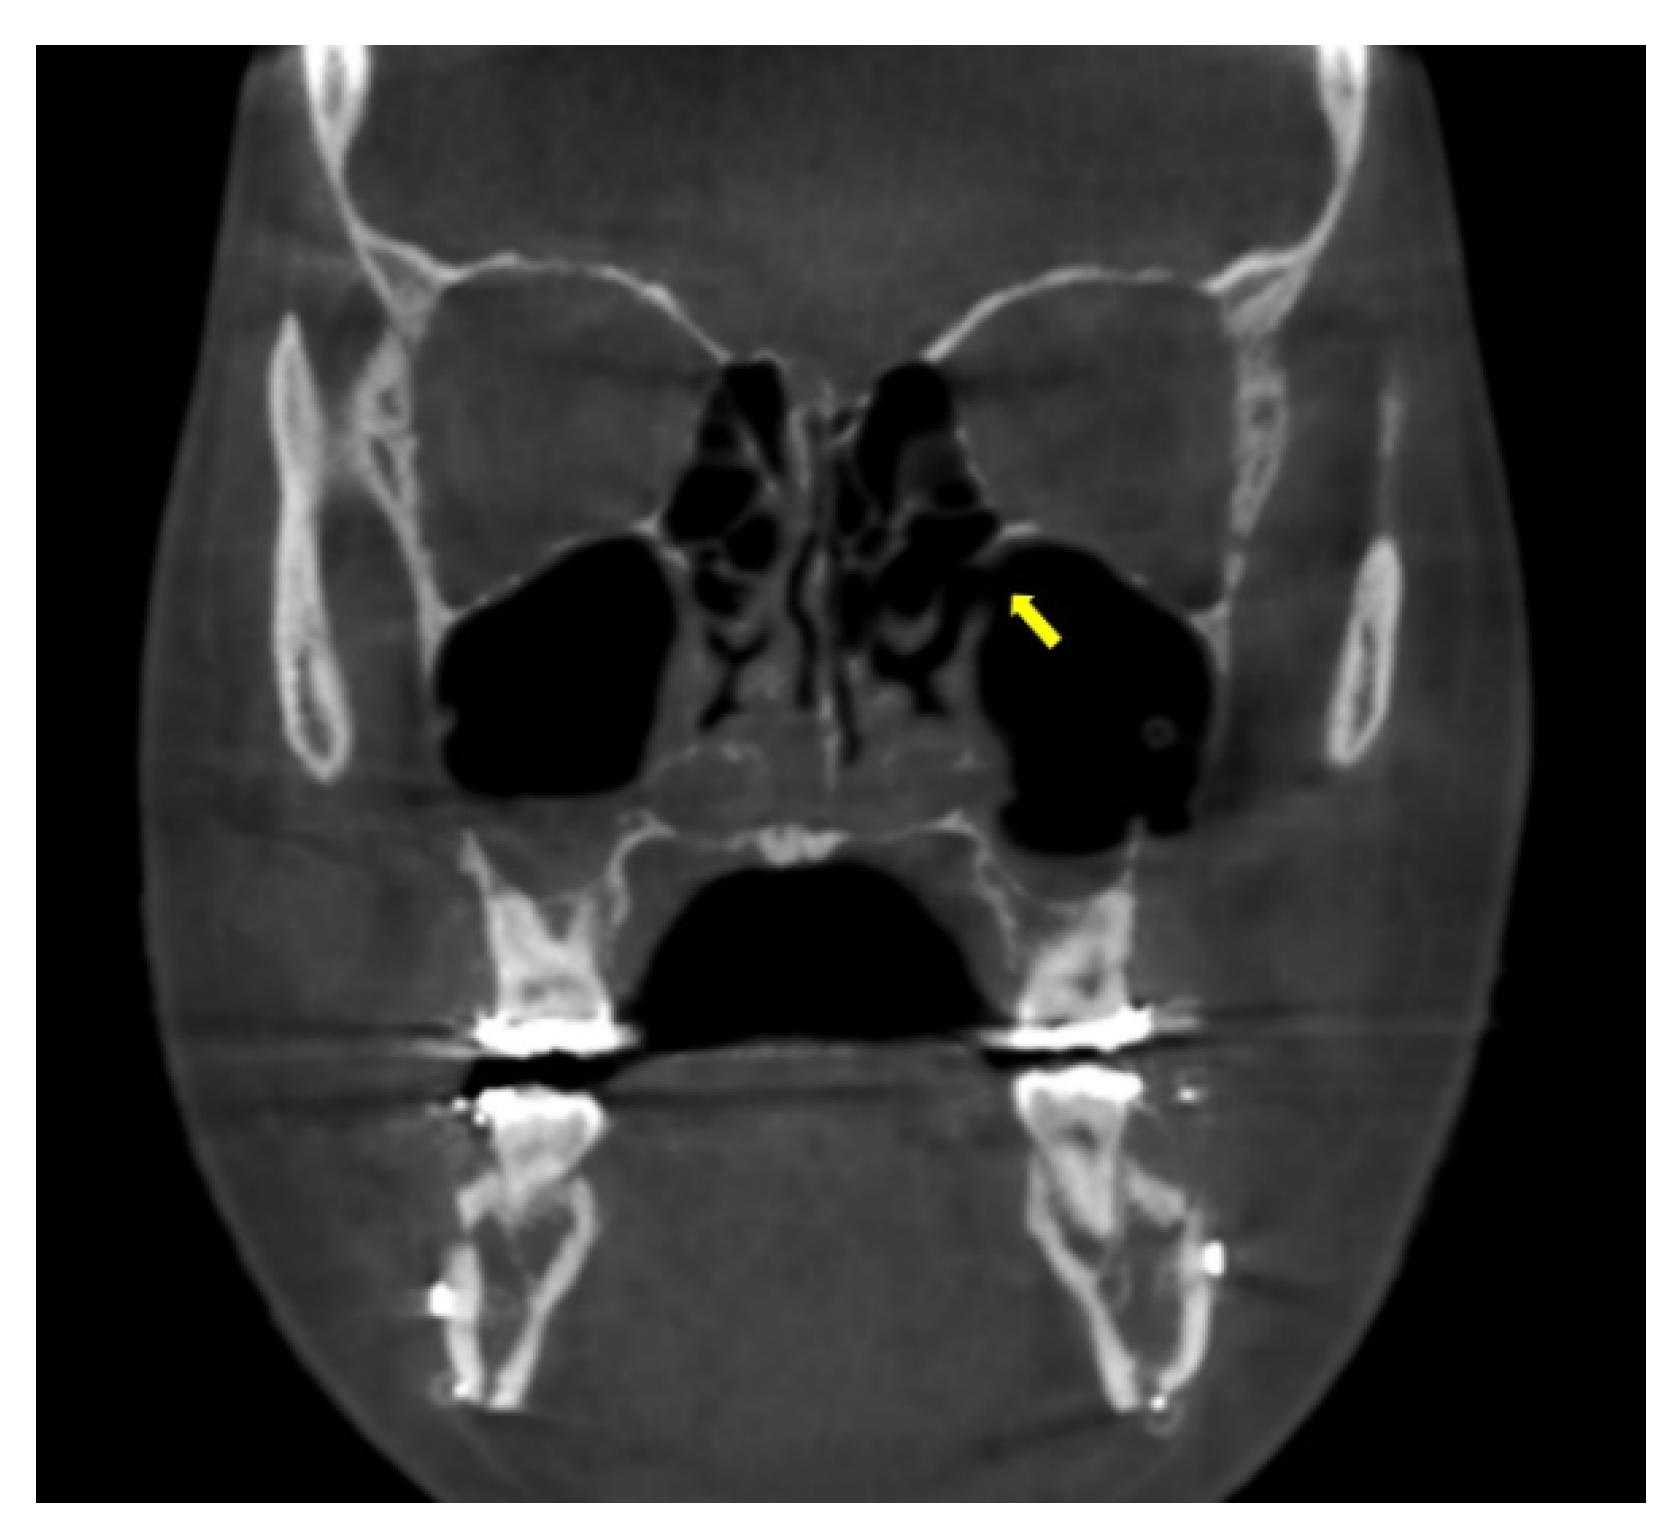

All patients underwent cone-beam computerized tomogram (CBCT, Kavo 3D exam, 37.10 mAs, 120 KVP, acquisition time 17.8 s) before and 2 days after bimaxillary orthognathic surgery. One of the authors analyzed the radiological features using 3D viewer software (Invivo®, Anatomage, San Jose, CA, USA). The middle meatus patency and the ratio of air volume per total maxillary sinus volume were also determined. On coronal view, the patency from the maxillary sinus to the nasal airway was evaluated (Figure 4). The entire maxillary sinus volume before the surgery was analyzed by CBCT using a 3D-volume measuring system for the right and left sides separately. The air volume of the maxillary sinus was evaluated 2 days after surgery with the same method. Further, air volume as per the entire maxillary sinus volume was calculated (Figure 5).

Figure 4.

The patency of middle meatus was confirmed on coronal view of cone-beam computed tomography 2 days after surgery (arrow).